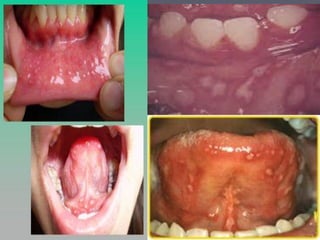

HERPANGINA

►   Erupción bucal causada x virus Coxackie A

►   Prevalencia estacional

►   Clínica:

 Fiebre de comienzo agudo

 Faringitis, disfagia

 Lesiones papulovesiculosas en cavidad oral posterior (sem), sin

gingivitis

 Síntomas sistémicos moderados

►   Autolimitado

►   Gingivoestomatitis herpética → Ulceras múltiples

superficiales generalizadas. Gingivitis marginal intensa.

ENF. MANO-PIE-BOCA

►   Virus Coxackie A16 o Enterovirus 71

►   P. Incubación 4-6d. Muy contagiosa

 Prodromo leve/ausente → Fiebre, anorexia, malestar

 Lesiones orales → Dolor de garganta, vesículas en mucosa de mejilla

y lengua

 Lesiones cutáneas → Vesiculopústulas blanco grisaceas elípticas en

palmas y plantas, tb gluteos y genitales. Asintomáticas/prurito.

Resolución en 3-7d sin dejar cicatriz.